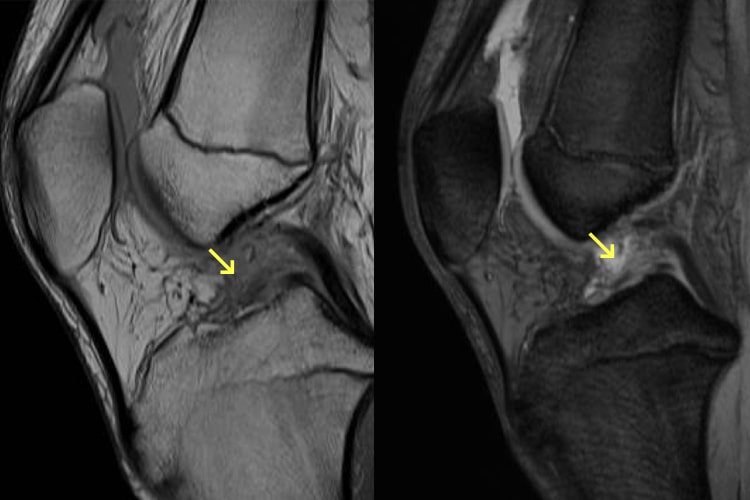

前十字靭帯損傷写真

外側半月板損傷

ジャンプの着地、急激な方向転換、急停止など非接触時に起こり、タックルを受けて膝の外反が強制される等、接触時に起こることもあります。受傷直後は著明な関節血腫に起因する関節痛が生じ、関節腫脹、運動障害や歩行障害も認めます。陳旧例では、関節の不安定性を訴え来院されることが多いです。日常生活やスポーツで膝関節にどの程度負荷をかけるかにより治療方法が決定されます。スポーツ愛好家ではない場合、大腿四頭筋やハムストリングスの筋力強化を徹底することにより手術を回避します。体育参加など膝のへの負荷を要求される時は、膝装具着用やテーピングの適応となります。一方、積極的なスポーツ参加者や、日常生活動作が障害される場合には手術が適応となります。手術の場合は靭帯の再建術を行い、細かいプロトコルに沿ってリハビリを行っていきます。